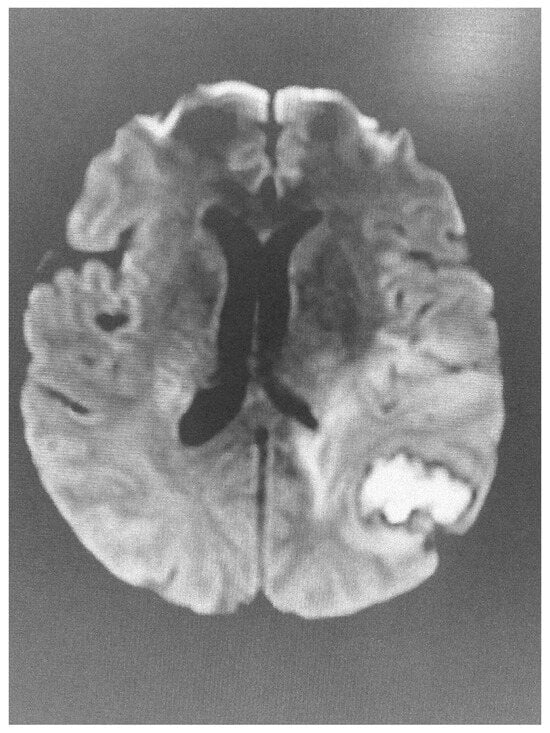

dMRI utilizes the anisotropic water diffusion in white matter to produce micro-architectural details of white matter tracts and provide information about white matter integrity [14]. Through dMRI, we can define the structural connectivity between various brain areas and perform a detailed mapping of the connectional pathways of the brain [15]. White matter connectivity differences were identified using dMRI in military personnel exposed to trauma with or without post-traumatic stress disorder [16]. Furthermore, repeated overstimulation of the stress system, caused by prolonged exposure to highly stressful experiences, may affect brain structure, cognitive function and mental health. According to UK Biobank data, there is a clear link between stress and changes in brain microstructure, impairment in cognitive function and negative mental health outcomes [17]. Sex plays a distinct role in this reaction. Females and males present significant differences in white matter integrity when exposed to low levels of early life stress, with females showing lower white matter integrity compared with males. No difference in white matter integrity is observed in males and females exposed to mild stress. However, males are more sensitive to early life stress, while females are more sensitive if early life stress is followed by stress in adult life [18]. Diffusion images have been also used to clarify the acuity of lesions identified using FLAIR imaging (Figure 1 and Figure 2).

Figure 2. Abnormal diffusion image of the brain in the same patient, indicative of acute lesion.